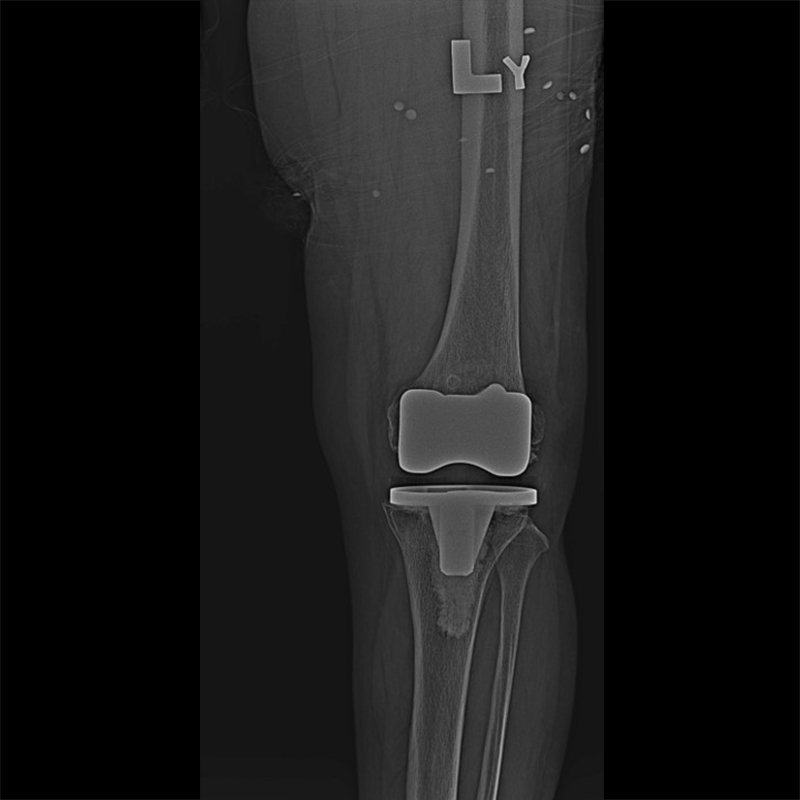

外院失敗本院再置換 首頁 案例分享 膝關節手術 外院失敗本院再置換 蕭女士 69歲 術前 術後 81歲 林女士 術前 術後 蕭女士 69歲 術前 術後 鄒女士 69歲 術前 術後 李女士 74歲 術前 術後 吳女士 71歲 術前 術後 謝女士 65歲 術前 術後